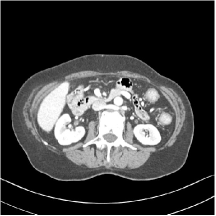

III.C. Low-dose Experiments with Mayo Clinic Data

First, we study transform training based on Mayo Clinic data. As shown in Fig. 6, seven slices obtained at regular dose from three patients are used for transform learning. The number of pixels . Similar to the phantom experiments, overlapping patches are extracted with a patch stride. The number of overall training patches is about . We set for ST, , , for MARS2, , , , , for MARS3, , , , , , , , , for MARS5, , , , , , , , , , , , , for MARS7. The iteration number in Algorithm 1. Fig. 7 illustrates the learned transforms obtained with Mayo Clinic data. Different from the XCAT phantom case, these transforms up to MARS5 display more complex features and structures. The rich features of the MARS models better sparsify the training images over layers compared to the single-layer model (ST).